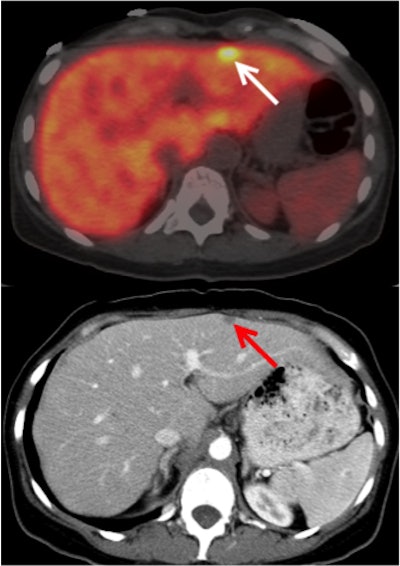

Lohrmann and colleagues investigated HuMab-5B1 with and without radiolabeling with zirconium-89 (Zr-89 DFO HuMab-5B1). Nine patients with metastatic malignancies that were positive for CA 19-9 received four whole-body PET/CT scans, the first performed on the first day of injection with the imaging agent, and then again on day 2 and around days 4 and 7. Individuals also had CT scans before the baseline PET/CT, which were used to verify the results of the radiotracer.

The researchers measured maximum standardized uptake values (SUVmax) for uptake of the agent in tumors. They found significant tracer uptake in local tumor recurrences, as well as in metastases. Uptake was analyzed for a total of 52 lesions; the highest uptake was seen on day 7 in the lymph nodes.

PET/CT with Zr-89 DFO HuMab-5B1 led to the detection of very small tumors in the peritoneum and mesenteric lymph nodes that weren't found by CT alone, the researchers found. They concluded that the radiotracer could lead to improvements in the management of pancreatic cancer, including better tumor staging, improved surgical guidance, restaging of metastases, and potential drug selection for therapies that target CA 19-9.